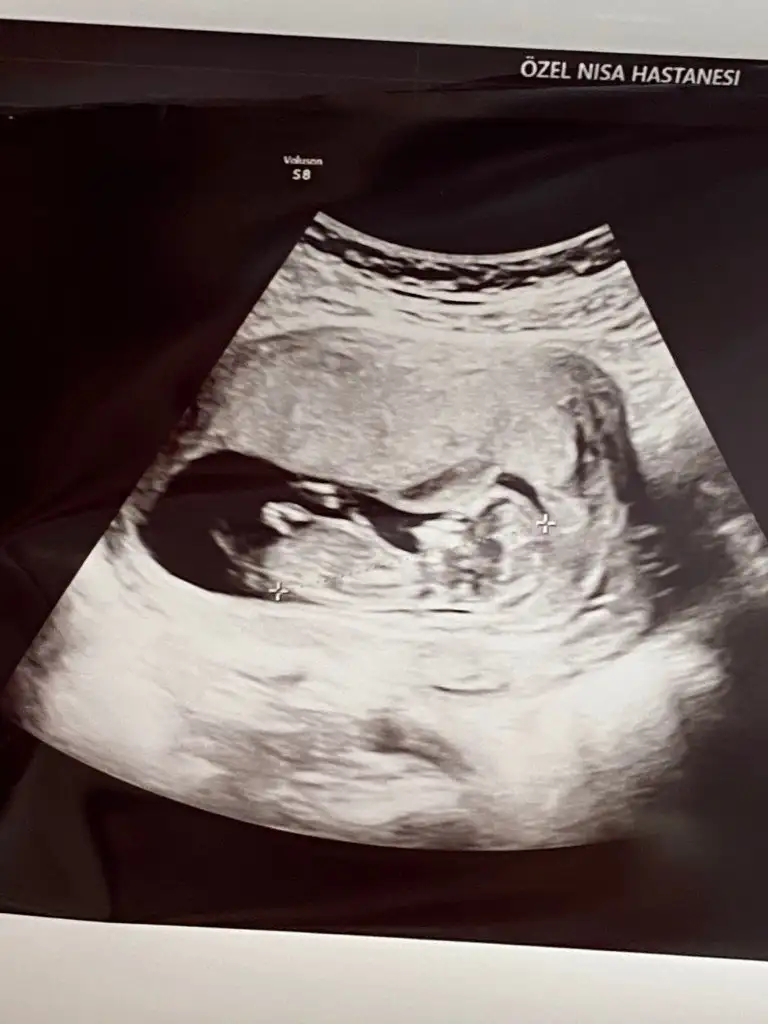

Cinsiyet tahmini alalim 12 hafta

Bence tam görememiştir doktor çünkü mutlaka yukarı doğru bir çıkıntısı oluyo 11-12 de bile belli oluyor ama pozisyon önemli tabii birde doktorun ultrason cihazın kalitesi

12. Hafta da cinsiyet çok.net.olmuyor. ilk gittiğim doktor 12. Hafta da kız demişti. Ama 15. Haftaki kontrolde erkek dedi başka bir doktor nitekim oğlum oldu.